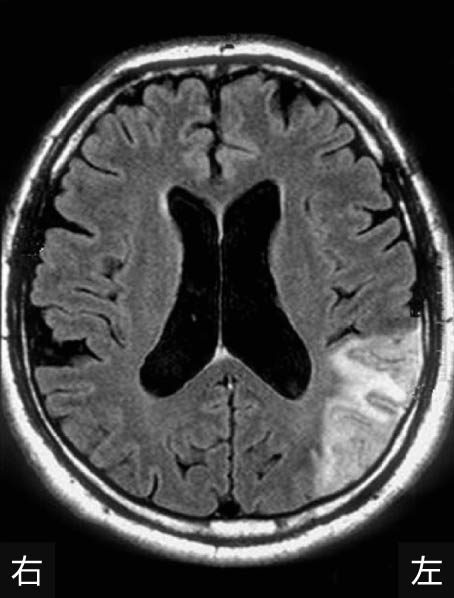

60歳の男性.右利き.脳梗塞を発症し,回復期リハビリテーション病棟に入院中である.食事時に右手でスプーンの柄を握りこんでしまい,うまくスプーン操作ができず,介助が必要になることが多いが,少しずつ食事動作が円滑にできる場面が増えてきている.頭部MRIを下に示す.この食事動作の病態として